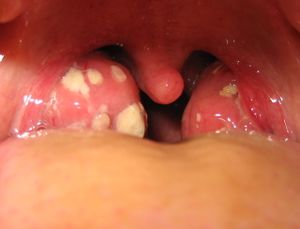

Enlarged, red tonsils and exudative white patches of tonsillitis

1. ضخامة اللوزتين التي قد تكون أحياناً شديدة جداً.

2. احمرار اللوزتين مع وجود بقع بيضاء قيحية عليهما.

(التشخيص) يتم التشخيص بسهولة بفحص الفم مع استخدام خافض اللسان حيث تشاهد اللوزتان المتضخمتان مع وجود احمرار فيهما وبقع بيضاء قيحية أحياناً وقد نجد احمراراً في البلعوم أيضاً أما تأكيد سبب الالتهاب فيحتاج لإجراء مسحة البلعوم (أي اخذ عينة في البلعوم أو اللوزتين وزرعها.